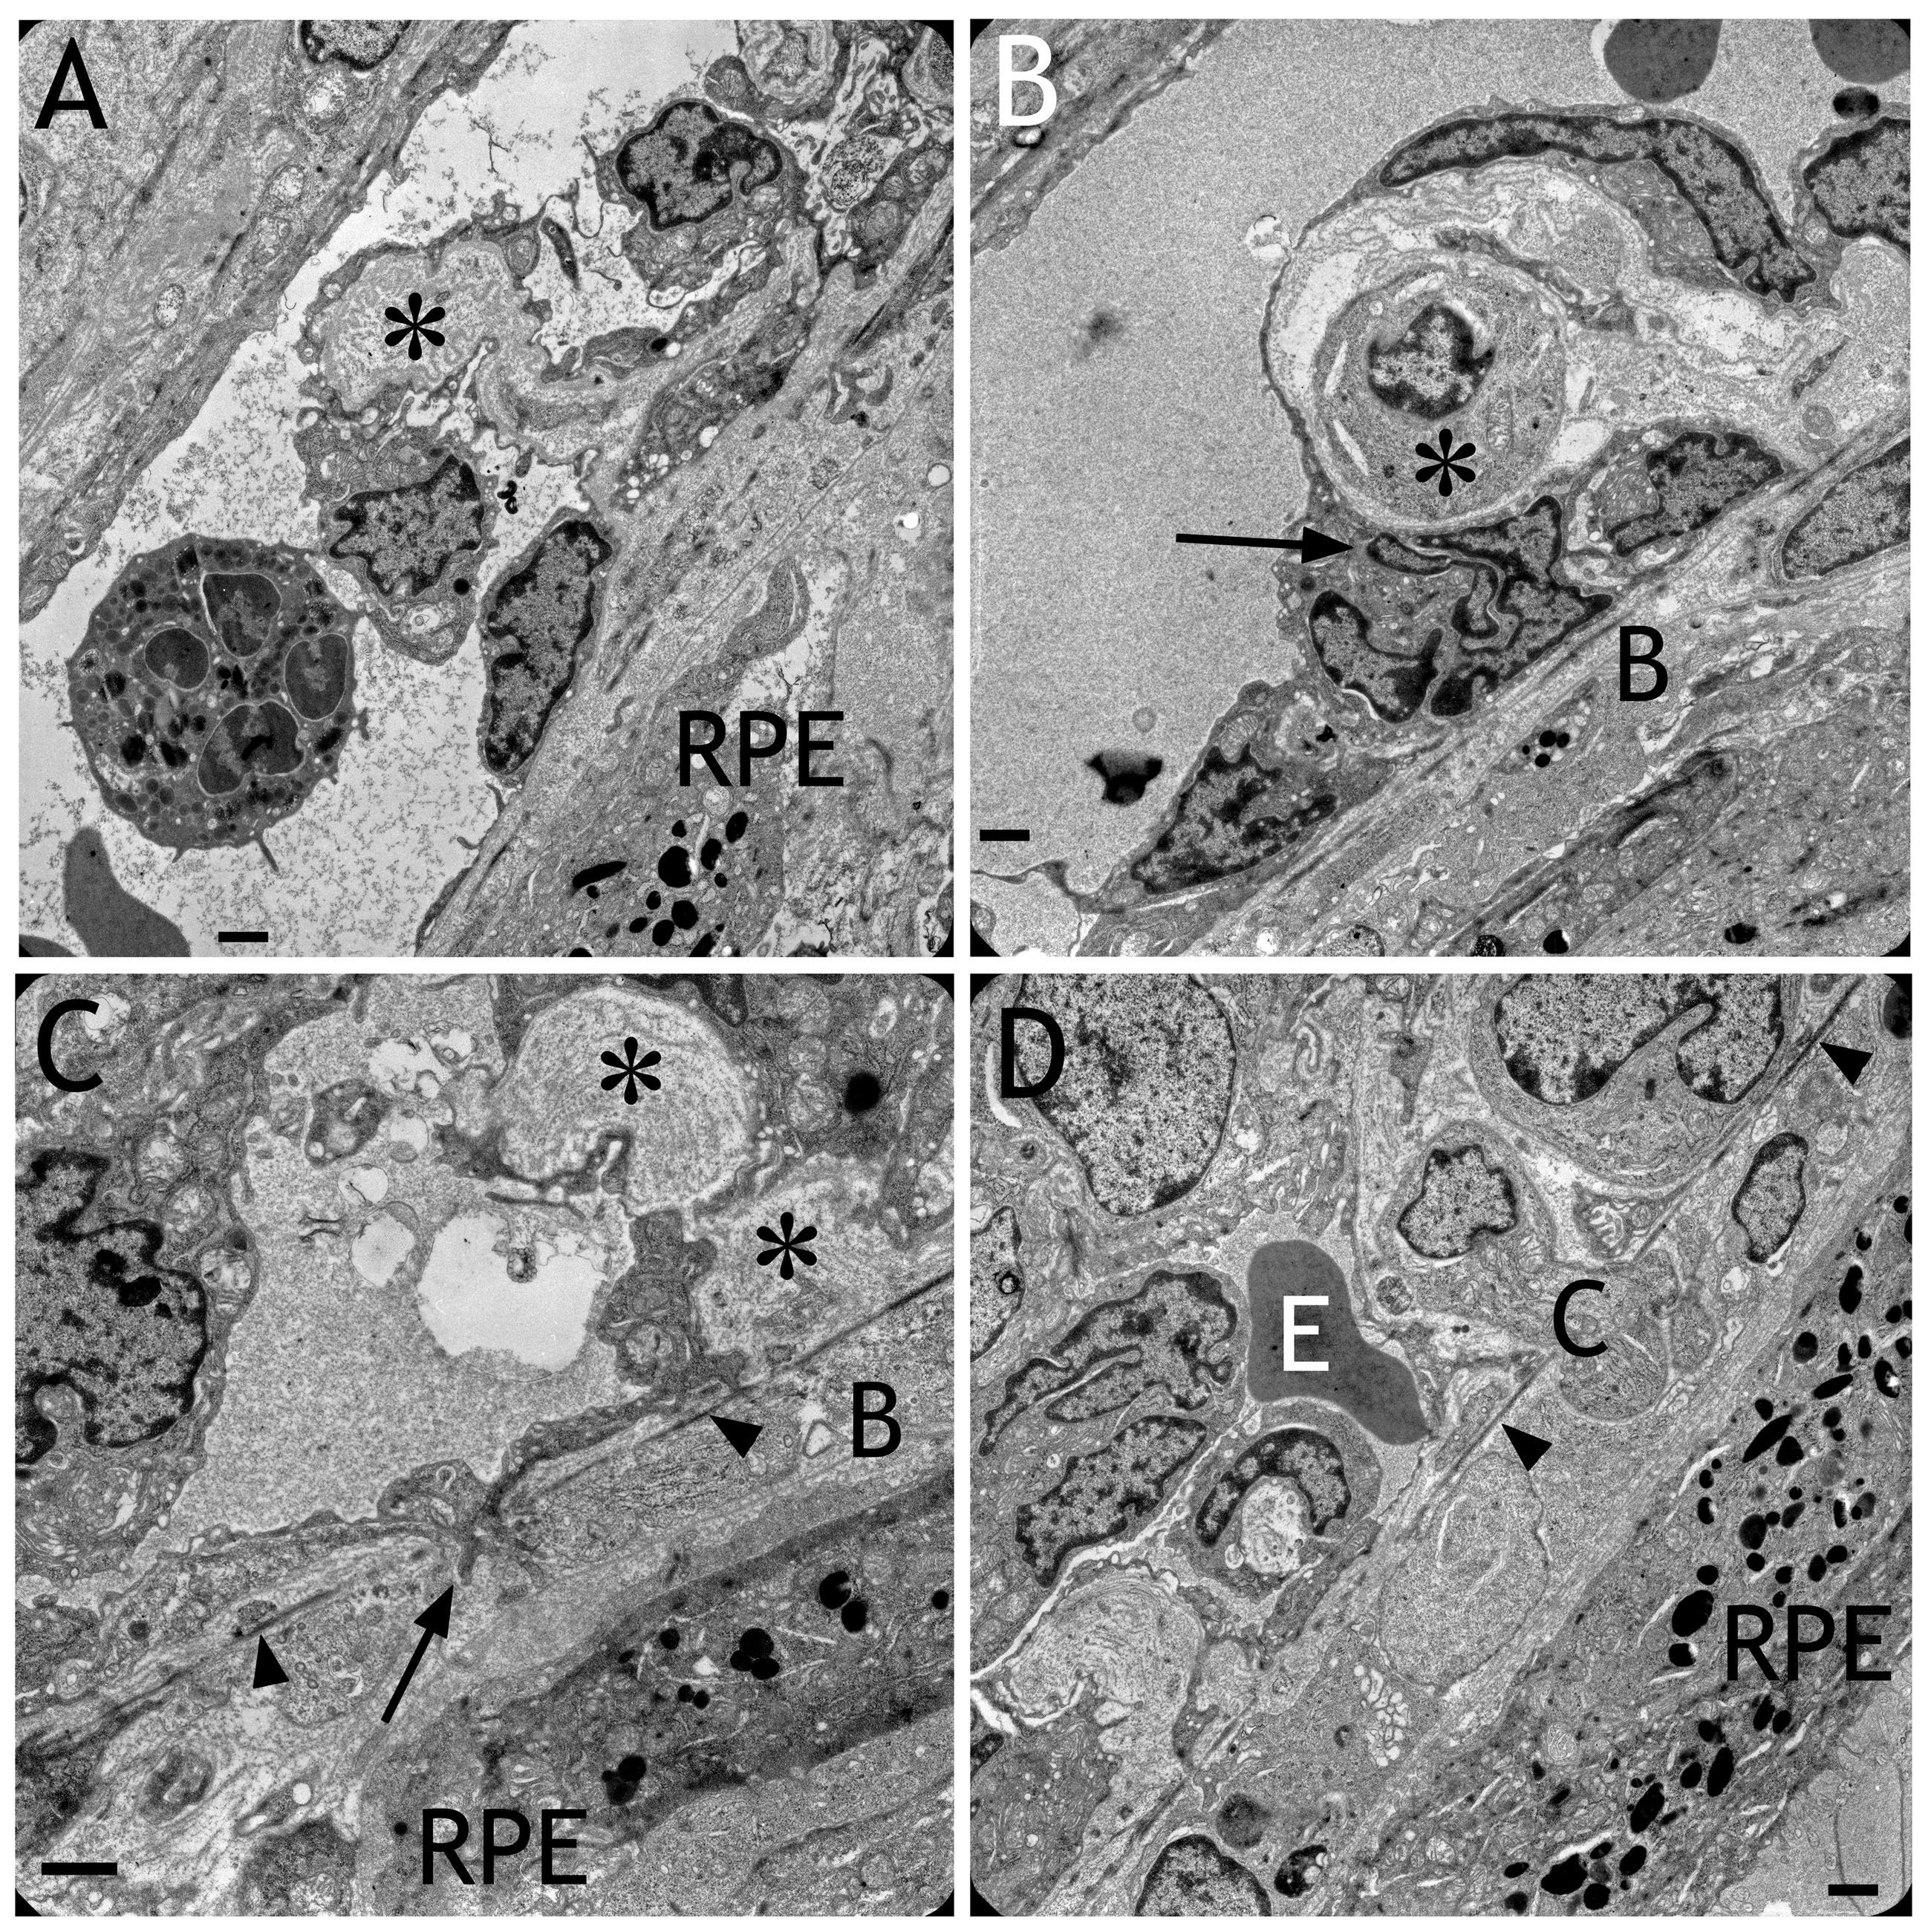

Figure 5 of Julien, Mol Vis 2008; 14:1358-1372.

Figure 5. Electron micrographs obtained after transduction with HC Ad.VEGF-A. A: An invagination of the the endothelium into the lumen of the choriocapillaris containing extracellular matrix (asterisk) is shown. This caused the patchy appearance of the choriocapillaris lumen presented in Figure 4. B: A cell (asterisk) was located between the endothelium and Bruch’s membrane. Note the extremely frayed or fragmented nucleus of an endothelial cell (arrow). C: An endothelial cell was spreading into Bruch’s membrane (B) toward the RPE (arrow). The elastic layer of Bruch’s membrane is labeled by arrowheads. Sites indicating remodeling of the extracellular matrix surrounding the choriocapillaris are labeled by asterisks. D: A cell (C) was migrating into Bruch’s membrane toward the RPE. The elastic layer of Bruch’s membrane is labeled by arrowheads. Within the pathological capillary, an erythrocyte (E) was still present. Scale bars in each image: 1 μm.